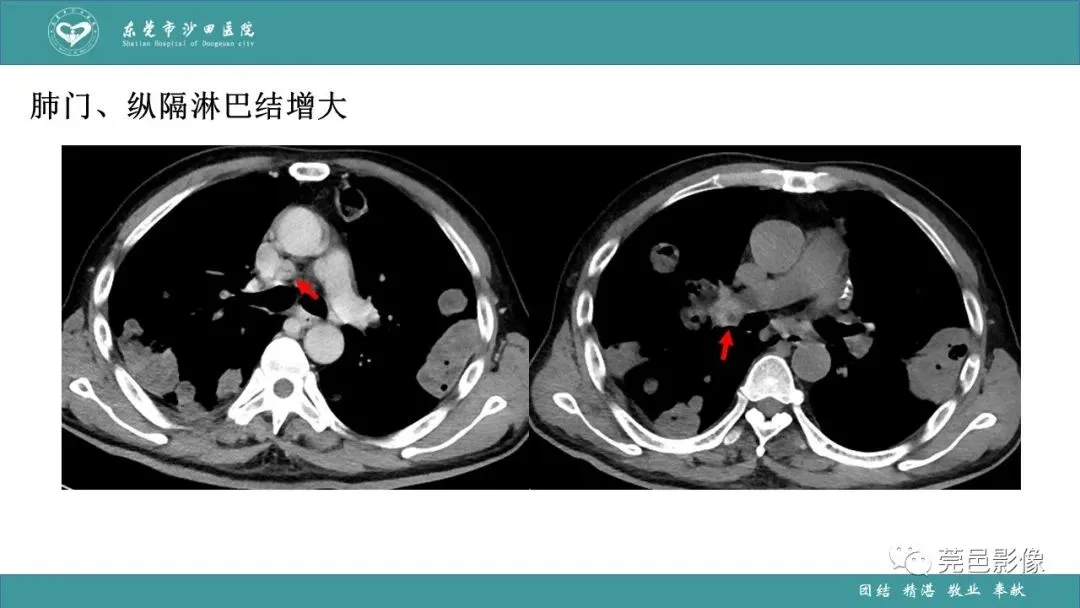

>课件 | 肺炎克雷伯杆菌肺炎影像学诊断与鉴别诊断

课件 | 肺炎克雷伯杆菌肺炎影像学诊断与鉴别诊断